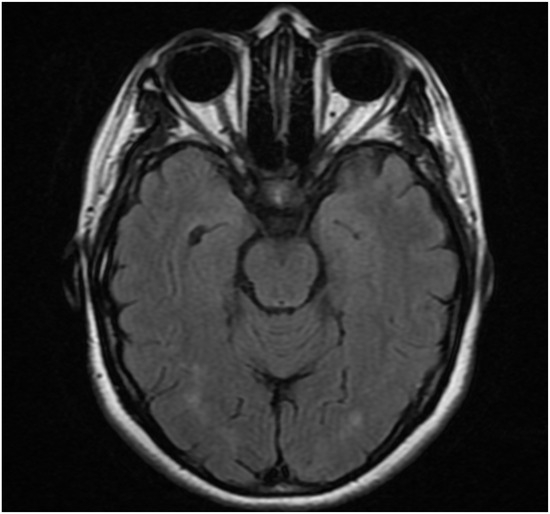

Background: Neuromyelitis optica spectrum disorder (NMOSD) is an autoimmune demyelinating disease with important disability accumulation. Early-onset NMOSD, defined as disease onset before age 50, exhibits distinct clinical characteristics compared to late-onset disease. We present a case series of patients with first symptom onset

Background: Neuromyelitis optica spectrum disorder (NMOSD) is an autoimmune demyelinating disease with important disability accumulation. Early-onset NMOSD, defined as disease onset before age 50, exhibits distinct clinical characteristics compared to late-onset disease. We present a case series of patients with first symptom onset before age 30. Methods: A retrospective review of 10 patients diagnosed with NMOSD at our center in San Luis Potosí, Mexico, with disease onset before age 30. Clinical presentation, imaging findings, AQP4 antibody status, treatment response, and disability outcomes were analyzed. Results: The mean age at onset was 18.6 years (range 6–30). Area postrema syndrome was the most common presentation (40%), followed by acute myelitis and optic neuritis (30% each). All tested patients were AQP4-positive. The mean EDSS at follow-up was 6.6, indicating severe disability. Most patients received rituximab with variable response rates. Conclusions: Our cohort showed higher disability than reported in other early-onset series, emphasizing the need for prompt diagnosis and aggressive treatment in this population.

Figure 1